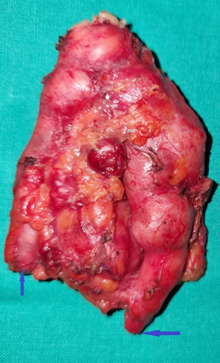

Εκτεθέν λειομυοσάρκωμα αριστερής περιοχής ώμου (Ευγενική παραχώρηση Dr. V. Penopoulos)